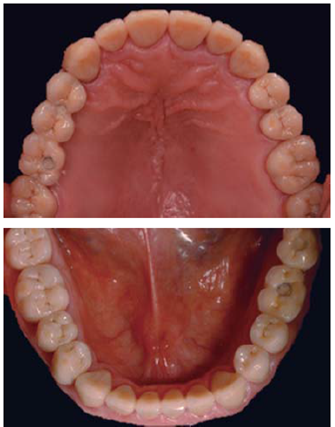

Se optó por disilicato de litio como sistema restaurador definitivo (coronas IPS e.max™ monolíticas, maquilladas en sector posterior y estratificadas en anterior). El medio cementante seleccionado fue RelyX Ultimate™ (Figuras 33a36).

Las restauraciones implantosoportadas de los sitios 36 y 37 fueron confeccionadas en metal-cerámica, ferulizadas y atornilladas (Figuras 37y38). Sus tornillos de fijación se torquearon a 30 N como lo indica su casa comercial BTI, la chimenea se obturó con teflón y Clip F® de la marca Voco como material provisional.

Respetando los tiempos que una regeneración ósea guiada implica, los implantes en zona de 16 y 14 fueron cargados transcurridos seis meses de su colocación con segmento protésico implantosoportado, metalocerámico, ferulizado y atornillado (Figura 39).

El segmento protésico tuvo como pilares los implantes ubicados en zona de 14 y 16, mientras que la zona de 15 fue un póntico. Una vez verificado el asentamiento de los aditamentos, así como de la estructura metálica (Figura 40), se indicó el montaje de porcelana, se realizó prueba de la prótesis en boca y satisfechos los parámetros de color, áreas de contacto, relación con el lecho periimplantario y oclusión que procedió a su atornillamiento con un torque de 30 N.

Se controló al paciente por espacio de un mes y medio para verificar su fase de adaptabilidad al tratamiento y su condición fue satisfactoriamente estable, cómoda y sobre todo funcional (Figuras 42a45).